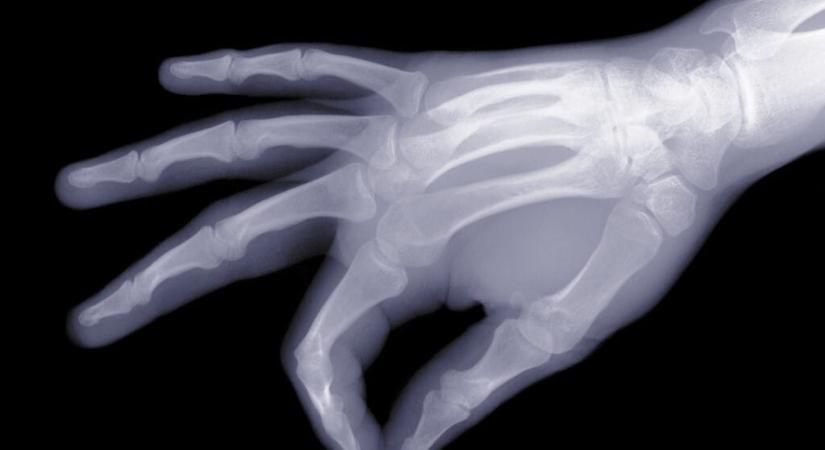

Olyat találtak az emberi csontokban, amit nagyon nem kellett volna

Brazil kutatók arra figyelmeztetnek, a mikroműanyagok már a csontokat is beszennyezik, ami számos problémát eredményezhet.